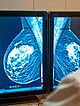

Wśród Polek najczęściej diagnozowanym nowotworem jest rak piersi. Każdego roku słyszy o nim ponad 21 tysięcy kobiet[1] – to ponad dwukrotnie więcej niż w przypadku raka płuca, drugiego na liście…

Postęp w leczeniu raka piersi

Postęp w leczeniu raka piersi jest ogromny i przekłada się na realne leczenie. W Polsce brakuje jednak specjalistów onkologii klinicznej i łatwego dostępu do najnowocześniejszych terapii. Ewolucja…